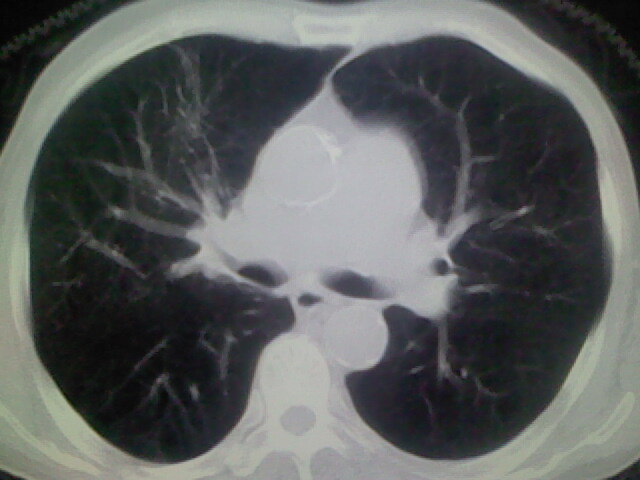

男,70y,胃占位,重度贫血,黑便3月余,伴恶心,纳差,乏力

1)考虑右肺上叶周围型肺癌并纵隔及右颈部淋巴结转移,肝脏多发性转移。2)肺气肿。3)冠状动脉及主动脉钙化。

支持右肺上叶周围型肺癌伴肝内多发转移.胃建议充盈后重扫描.慢性支气管炎伴肺气肿.

1)考虑右肺上叶周围型肺癌并纵隔及右颈部淋巴结转移,肝脏多发性转移。2)肺气肿。3)冠状动脉及主动脉钙化。胃未充盈而且影像不太清楚,不好确定